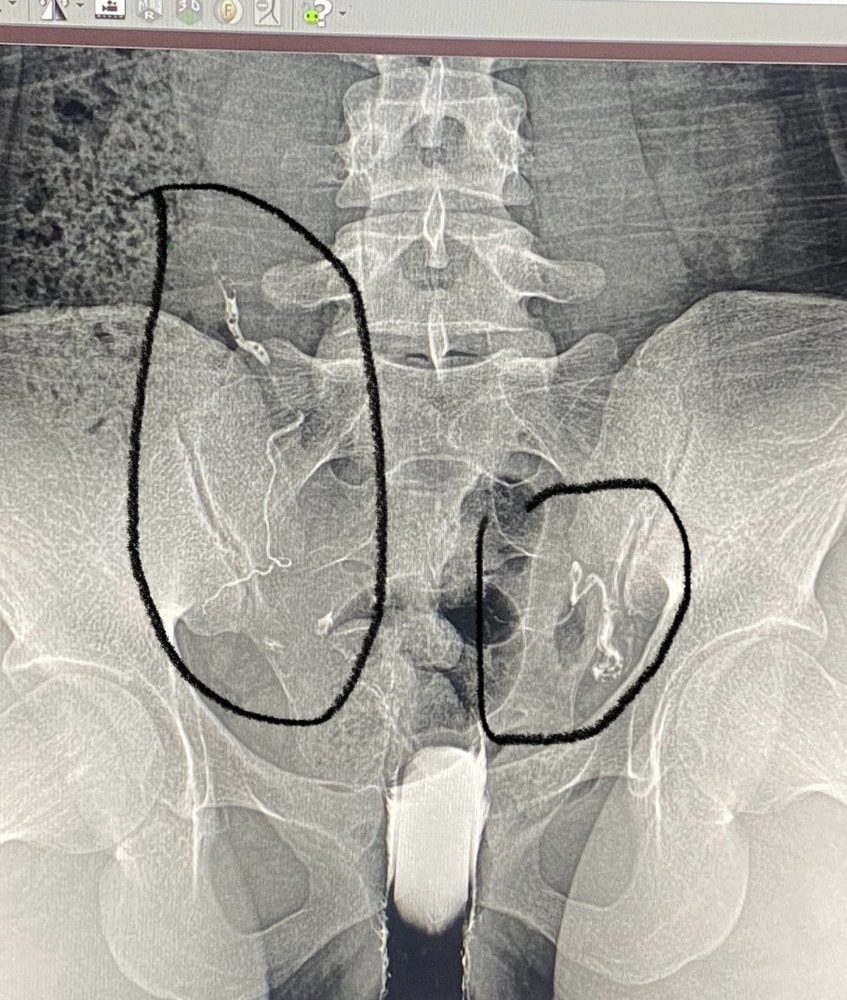

врач говорит проверить маточные трубы

насколько неприятная процедура и как лучше делать с узи или через рентген ?